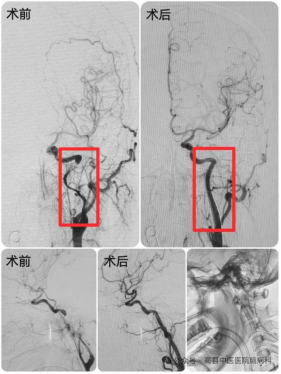

48岁的某女士,入院前3小时突发言语不清,头痛,口角稍向左侧歪斜,伸舌右偏,考虑为急性脑梗死。在排除溶栓禁忌症并与家属沟通后,予以溶栓治疗。溶栓后磁共振检查显示:左侧颈内动脉重度狭窄,局部闭塞,左侧大脑前动脉A1段局部轻度狭窄。脑病科团队迅速组织讨论,考虑到左侧颈内动脉次全闭塞,随时有栓子脱落、闭塞加重的可能,随后立即与家属沟通后,联合麻醉科团队予以介入治疗,成功开通了闭塞的血管!在脑病科医护团队的精心治疗及护理下,如今,某女士病情好转,言语清晰,活动自如。